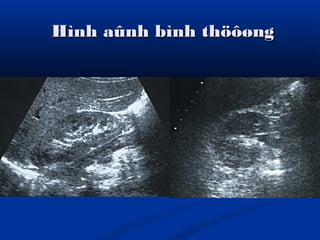

Hình aûnh bình thöôøngHình aûnh bình thöôøng